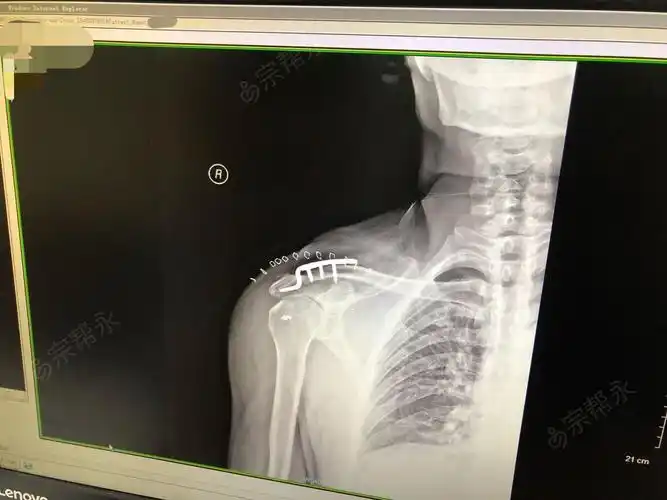

右肩锁关节脱位切开复位内固定术